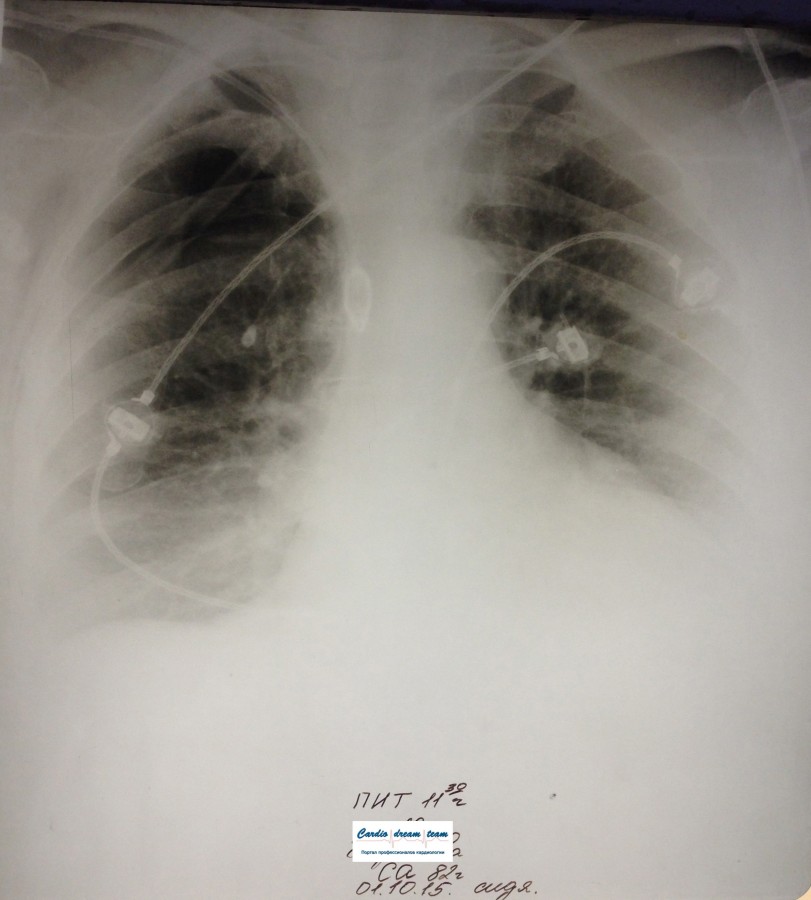

Проведена рентгенография органов грудной клетки в прямой проекции, положение полусидя, условия ПИТ, Р-контроль Легочные поля: Отрицательная динамика: правое легкое поджато к корню. Тень средостения резко смещена влево. Выраженная подкожная эмфизема мягких тканей грудной клетки справа. Тень подключичного катетера в проекции ВПВ. Легочный рисунок: диффузно деформирован за счет пневмосклероза, сгущен справа Корни: тень средостения смещена влево Синусы: нечеткие Сердце: широко лежит на диафрагме (позиционно) ЗАКЛЮЧЕНИЕ: Правосторонний пневмоторакс, отрицательная Р-динамика. Эмфизема мягких тканей грудной клетки. Пневмосклероз. Р-контроль.